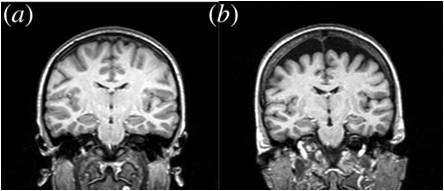

Selective atrophy of left hemisphere and frontal lobe of the brain in old men.

This is perhaps the single most compelling piece of evidence, an academic paper that quantifies the nature and degree of the catastrophic structural failure in our advanced new brain.

There are many more but this is one of the clearest and even has an image showing the degree of failure.

If you are unfamiliar with the language format or terminology you don't need to read the paper though a quick look at the abstract or introduction will confirm that the image (b) below shows massive loss of neural tissue from the most recent and advanced areas of the perceptual equipment you are using right now to take this test.